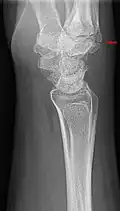

Carpal boss in plain X-Ray. -